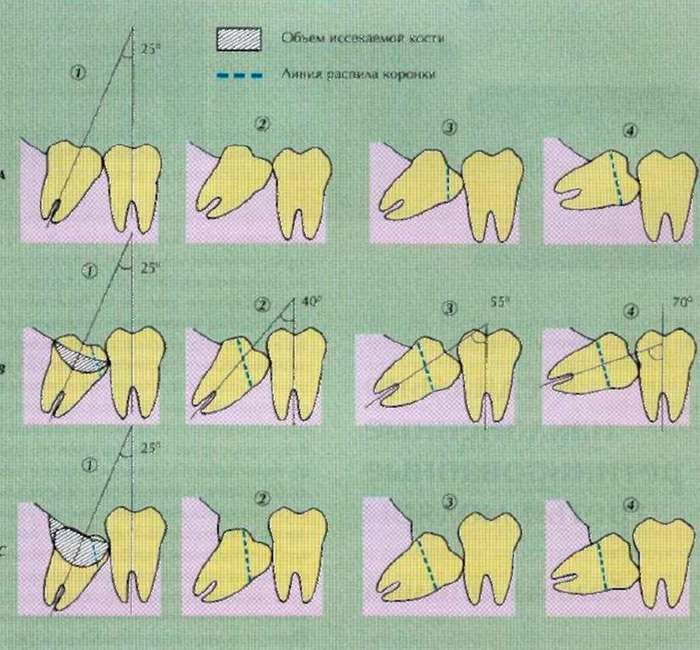

После того, как мы сделали анестезию, мы по необходимости производим разрез и отслаиваем слизистую оболочку с надкостницей от кости (слизисто-надкостничный лоскут) и бормашиной с водяным охлаждением выпиливаем костную стенку. Почему по необходимости? Потому что эти этапы зависят от степени прорезанности и расположения зуба. Чем более прорезан зуб, тем меньше разрез и меньше убираем кости. Иногда обходимся одним разрезом, иногда даже разрез не приходится делать, а просто распиливаем зуб. Короче, смотрим по ситуации.

По необходимости распиливаем сам зуб. Опять по необходимости? Конечно! Ведь надо смотреть по ситуации и соблюдать баланс между травматичностью и скоростью проведения операции. Если зуб лежит только под слизистой, корни сросшиеся и его можно достать элеватором, то не надо лишний раз его пилить. Достали, зашили и отпустили домой. Если же у нас зуб лежит криво и достать него просто так не получается, то тогда уже пилим либо зуб, либо подпиливаем кость.

Если у зуба растопырены корни, то их тоже надо разделять и по одному доставать, как в 30 главе.